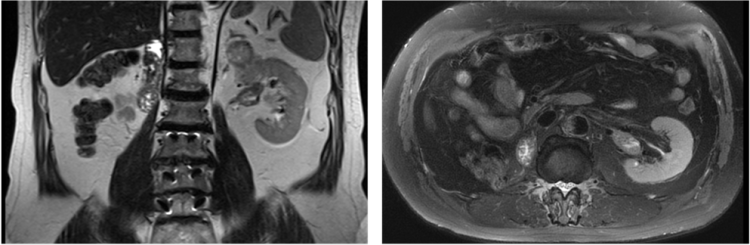

直到今年6月份,张先生的肾脏再次“报修”,左侧这颗宝贵的独肾也查出肿瘤,而且这次肾肿瘤也已经侵犯到肾静脉。

手术前,张先生经过为期5个疗程的靶向联合免疫新辅助治疗后,肿瘤及肾静脉内瘤栓均有缩小,血肌酐维持在140umol/L左右。